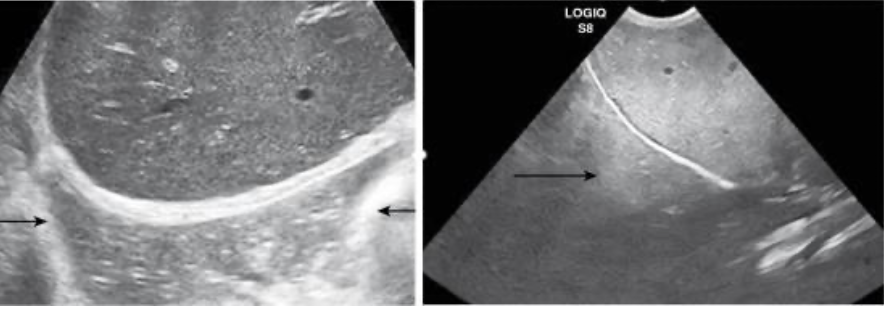

Acoustic Shadowing

occurs at interfaces that reflect and/or absorb a significant portion of the U/S beam

common with mineral interfaces (bones, calculi, foreign bodies)

Edge Shadowing

most common with round fluid filled structures

occurs at edge parallel to the sound beam

causes a dark shadow from edge of structure

gallbladder, urinary bladder, cysts, and sometimes kidneys